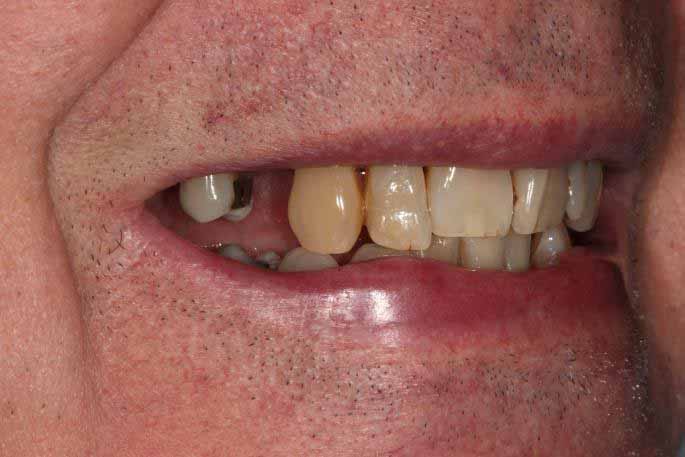

This patient had broken their upper front tooth and the exisitng dental crown had fallen off. The underlying root was unfortunatley irreparable.

The dental root was subsequently removed and an implant placed at the same time. The implant had a temporary crown placedon the same day.

The ‘After’ photos shows the final crown that was made after 3 months. The implant crown was made to match the form and colour of the exisiting teeth to give an overall natural aesthetic finish.